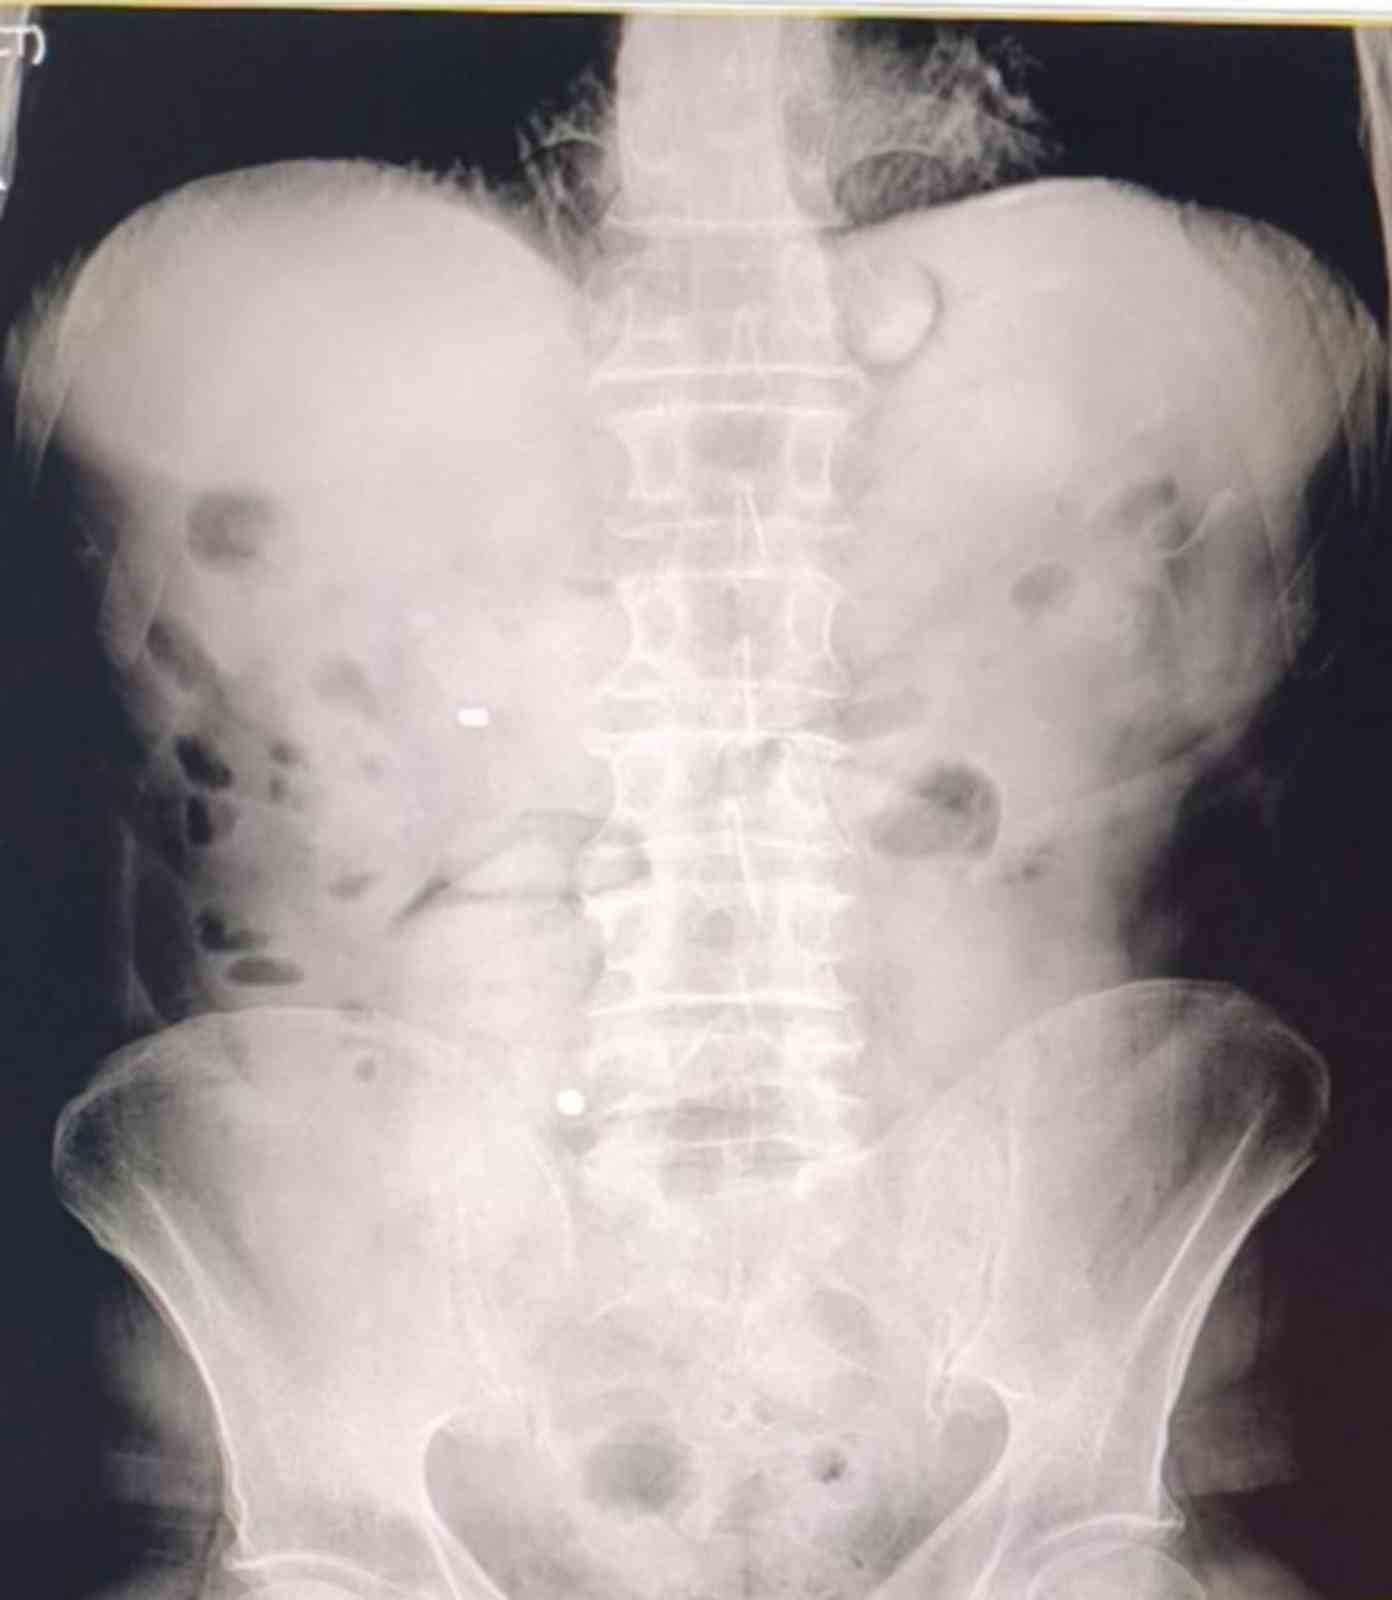

Şüphelilerin hastanede yaptırılan kontrolleri ve çekilen röntgen filmleri sonucunda mide ve bağırsaklarında çok sayıda uyuşturucu madde içeren kapsül bulunduğu tespit edildi. Hastanede kontrollü şekilde gözetim altında tutulan şüphelilerden tıbbi müdahaleler neticesinde toplam 93 parça halinde 1 kilo 70 gram metamfetamin ele geçirildi.